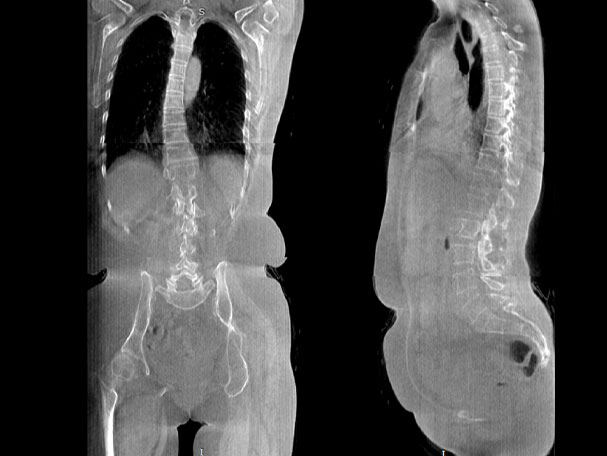

FOV 250mm

FOV 350mm